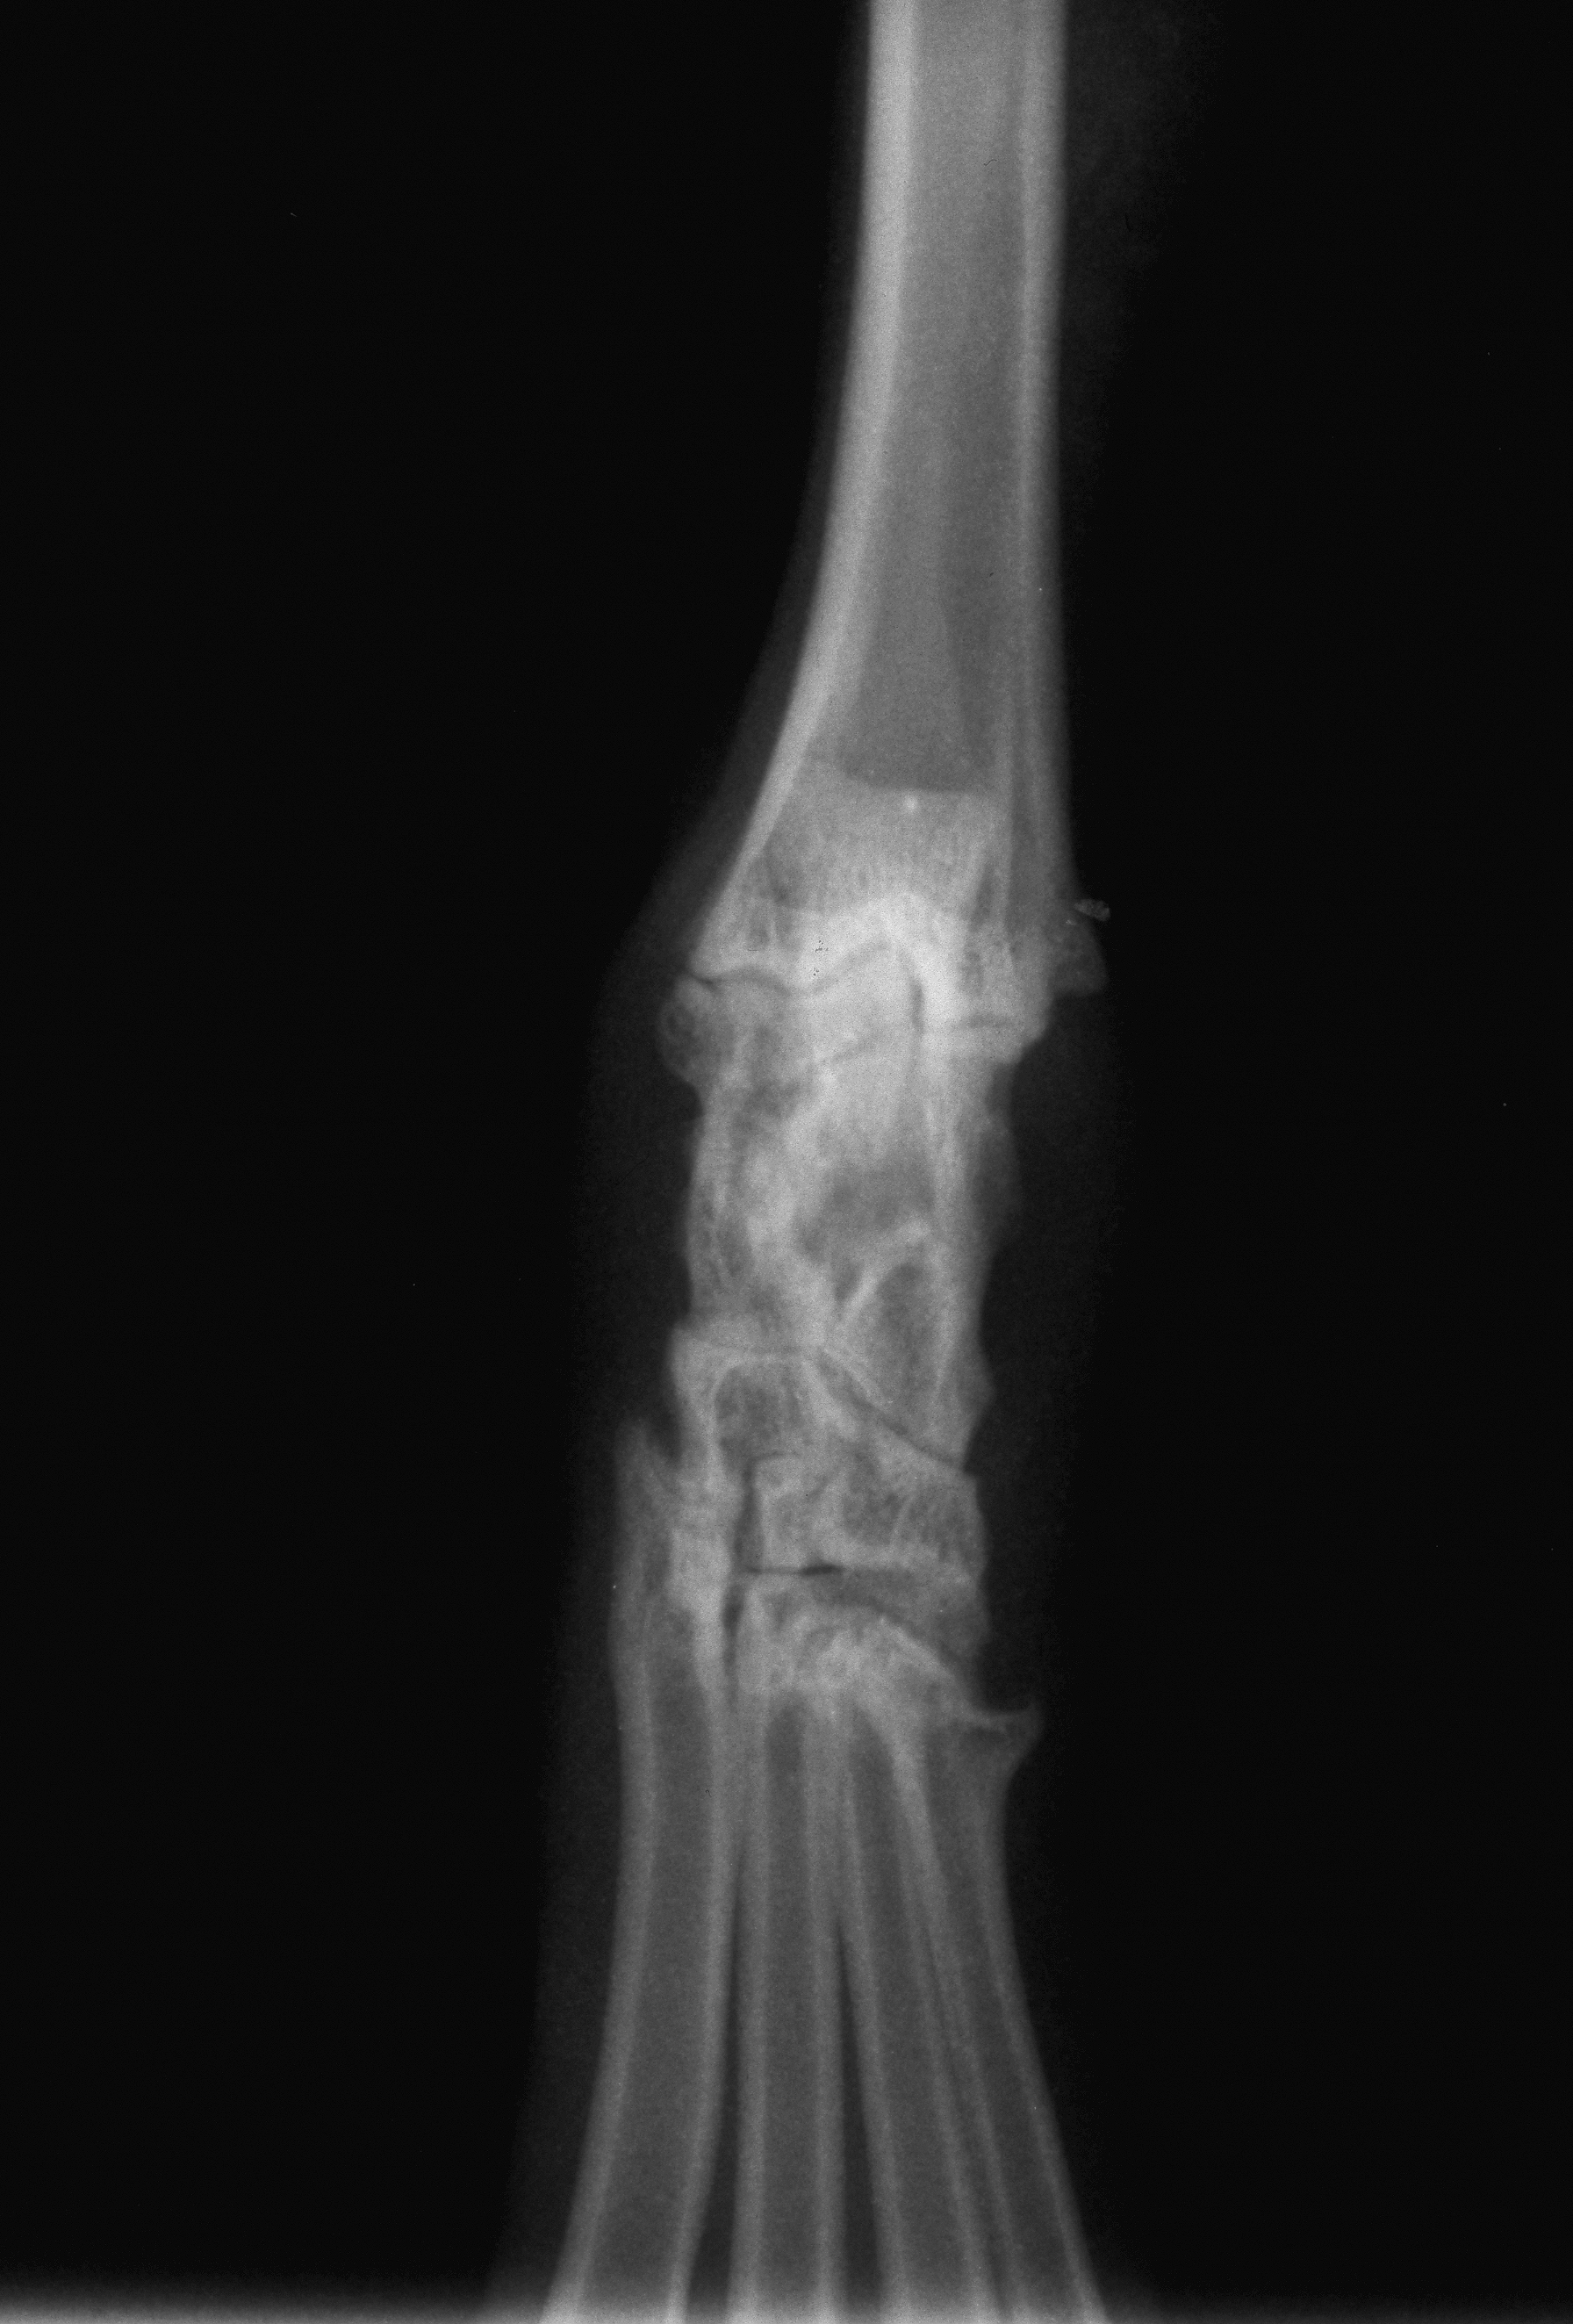

Normal hock vd

Radiograph

Orthopaedics